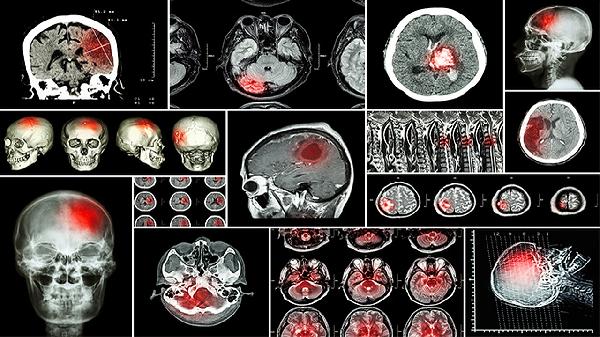

脑肿瘤会引起抽搐吗 脑肿瘤引起的5个症状细说

脑肿瘤可能会引起抽搐,常见症状主要有头痛、抽搐、肢体无力、视力下降、性格改变等。脑肿瘤是颅内异常生长的组织,可能压迫或破坏正常脑组织,导致多种神经系统症状。